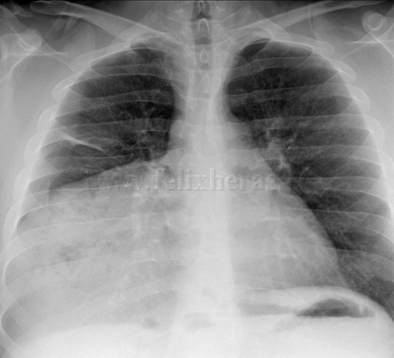

Hernia diafragmática traumática con laparocele gigante